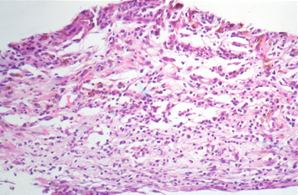

Figure 1. Immunostained surgically-excised inflammatory active CNV

A: Inflammatory active CNV with more inflammatory cells than fibrosis. (hematoxylin and eosin, 25x) B: There is VEGF expression in cells in the stroma, mainly macrophages and fibroblasts and some endothelial cells, as determined by cytologic characteristics [9]. (peroxidase anti-peroxidase, 63x) C: There are numerous cells in the stroma, mainly macrophages, expressing TF. (peroxidase anti-peroxidase, 63x) D: Negative control. (peroxidase anti-peroxidase, 63x)

A